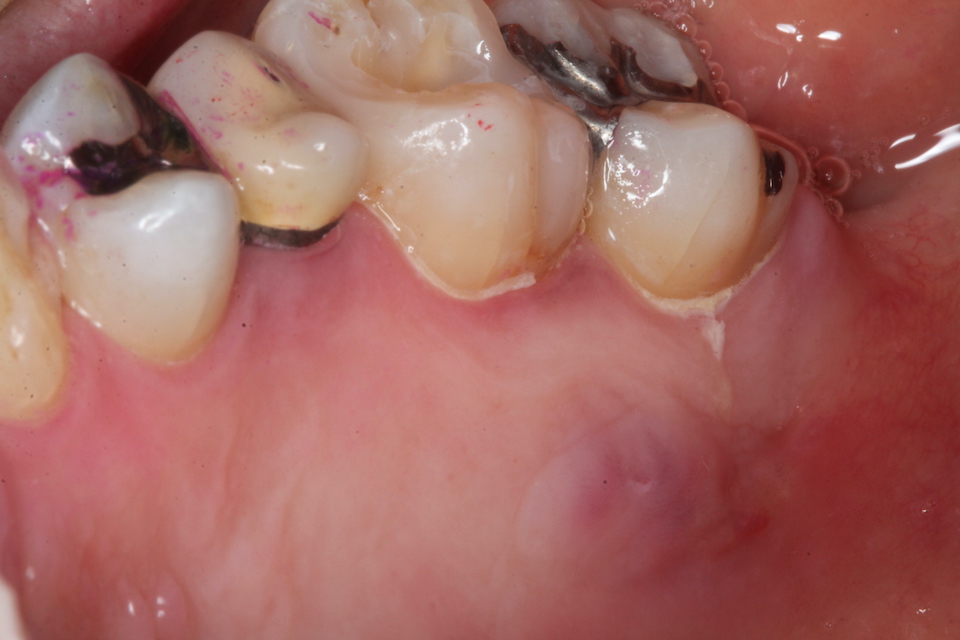

ブリッジ脱離で2次カリエス+Perでグラグ… 2025.11.01

ブリッジ脱離で2次カリエス+Perでグラグ… 2025.10.31